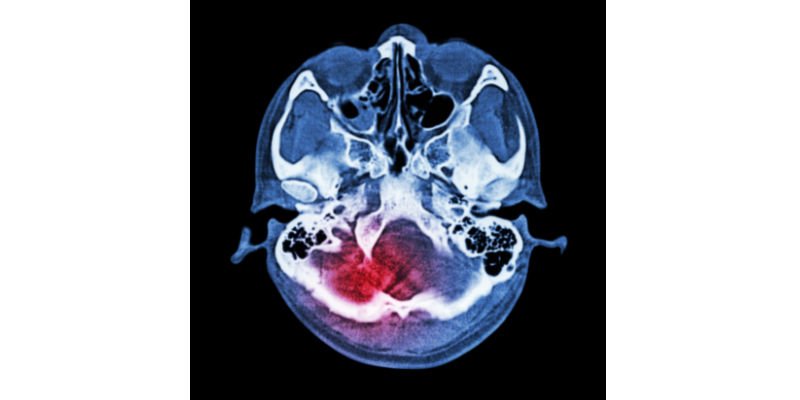

CHẤN THƯƠNG SỌ NÃO VÀ NHỮNG LƯU Ý MỌI NGƯỜI THƯỜNG HAY BỎ QUA

CHẤN THƯƠNG SỌ NÃO VÀ NHỮNG LƯU Ý MỌI NGƯỜI THƯỜNG HAY BỎ QUA 1/ Triệu chứng và phân loại chấn thương sọ não: Chấn thương sọ não... Đọc tiếp